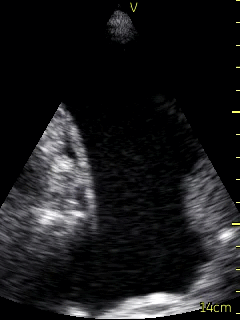

The patient’s right pleural space was assessed by the consultant Respirologist using a VScan device. A small amount of fluid in the right pleural space was noted to be gelatinous in appearance and loculated. Adjustment of the probe to the 6th intercostal space, roughly 10 cm from the spine helped to localize the largest fluid loculation in order to conduct the diagnostic thoracentesis (Figure 3, Video 3).  Following informed written consent, and lidocaine anesthesia in a sterile fashion, an angiocather was introduced guided by the ultrasound location of the largest pocket of fluid.  Approximately 70 ml of bloody fluid was collected.  The patient tolerated the procedure well without complication. Ultrasound post procedure persistence of fluid with several loculations remaining. The collected fluid was sent for routine analysis, cytology, flow cytometry, and culture.